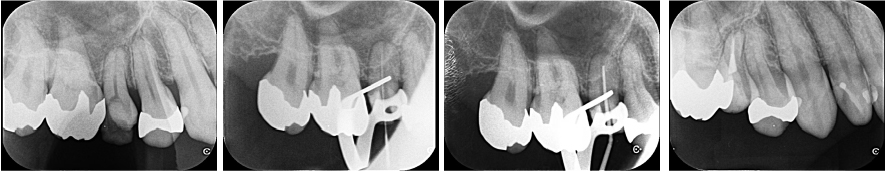

すでに複数回根管治療を受けていましたが、虫歯が残存しており、根管内には強く細菌感染が起こっていることが疑われる状態でした。根管自体は単根歯で複雑な形態ではなかったため、1回で根管治療を完了しました。

| 根管洗浄 | 次亜塩素酸ナトリウム溶液・EDTA溶液 |

| 根管貼薬 | なし(1回で治療を終えたため) |

| 拡大号数 | 40/04 |

| 根管充填 | バイオセラミックシーラーを用いたHydraulic condensation technique |